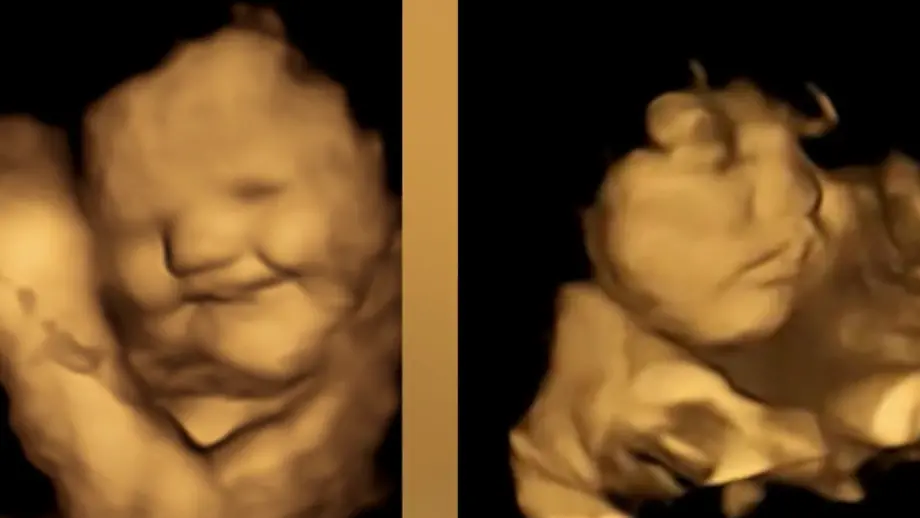

Die Nahrungsmittelvorlieben von Kindern prägen sich offenbar schon sehr früh aus. Einer Studie zufolge reagieren Babys bereits im Mutterleib positiv oder negativ auf manche Lebensmittel. So hätten Föten ein eher "lächelndes Gesicht" gezeigt, nachdem ihre Mütter Karotten gegessen hätten, berichten Wissenschaftlerinnen und Wissenschaftler der englischen Universität Durham in der Fachzeitschrift "Psychological Science". Nach dem Genuss von Kohl-Aromen hingegen hätten die Föten ein eher "weinendes Gesicht" gemacht.

Die Forscher zeichneten mithilfe von 4D-Ultraschallaufnahmen bei 100 Frauen die Gesichtsausdrücke ihrer Babys in der 32. sowie 36. Schwangerschaftswoche auf. Die Mütter erhielten rund 20 Minuten vor dem Scan eine Kapsel mit rund 400 Milligramm Karotten oder 400 Milligramm Kohlpulver und nahmen zudem eine Stunde zuvor nichts zu sich, das Geschmack enthält. Gesichtsreaktionen der Föten wurden mit denen einer Kontrollgruppe verglichen, die weder Karotten noch Kohl erhalten hatten.